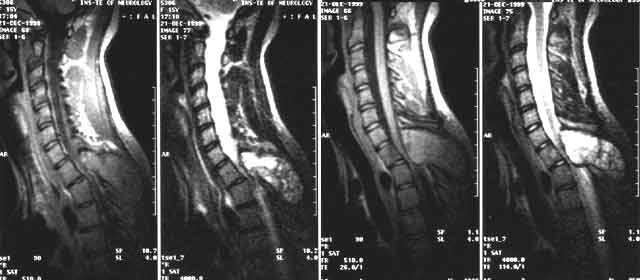

Врач проводит неврологическое обследование, пальпацию позвоночной области и сбор анамнеза, а также назначает ряд лабораторных и инструментальных исследований:

- рентгенография;

- сцинтиграфия;

- компьютерная томография (КТ);

- магнитно-резонансная томография (МРТ);

- общий и биохимический анализы крови;

- анализы на онкомаркеры.